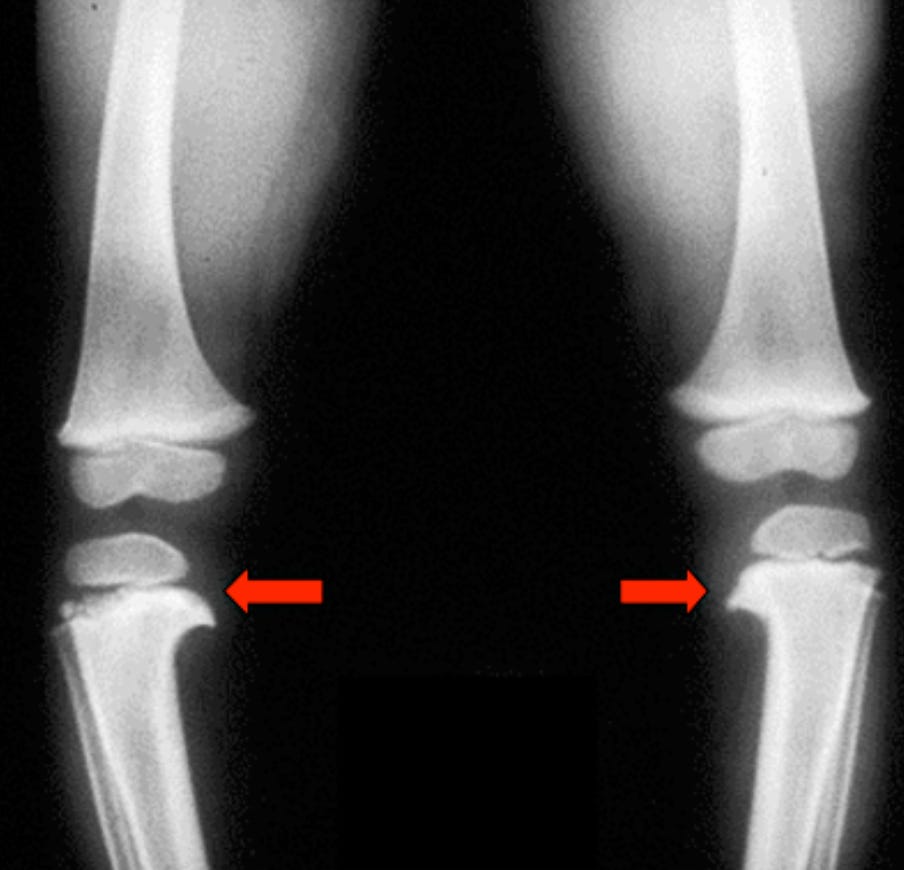

Варусная деформация проксимального отдела большеберцовой кости

Медиальное "клювовидное" выпячивание проксимального метафиза большеберцовой кости

Нисходящий наклон проксимального метафиза большеберцовой кости

МД угол большеберцовой кости >16° (хотя этот признак не является диагностическим)

Соотношение МД углов бедро:голень <1

Асимметричная угловая деформация нижних конечностей

Угловая деформация в проксимальном отделе большеберцовой кости